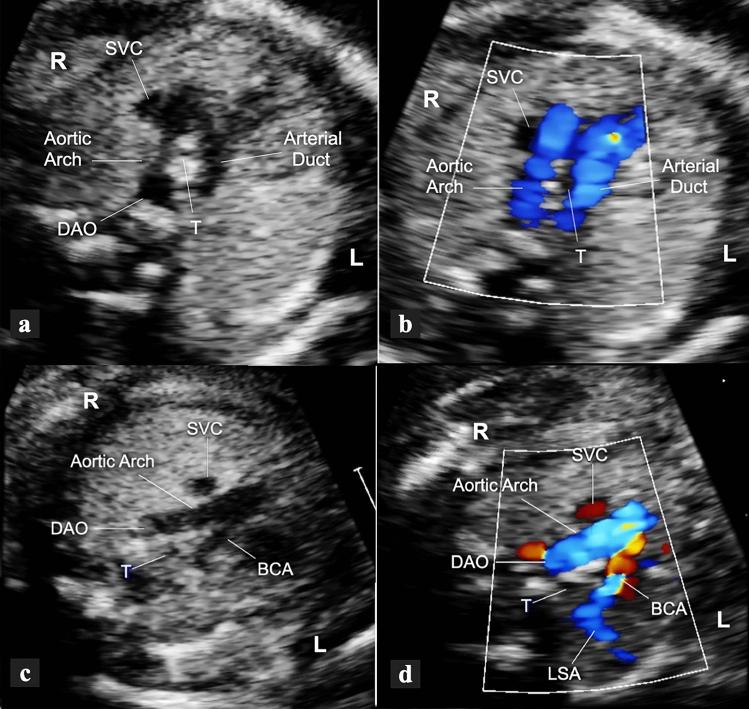

To study the different characteristics of arterial duct (AD) in a series of prenatally detected right aortic arch (RAA). Out of 832 congenital heart diseases (CHD) referred to a tertiary center, 98 cases had RAA. Based on anatomical landmarks we identified 7 types of AD: type 1 left-sided, transverse; type 2 left-sided, vertical; type 3 from the underside of aortic arch (AA), vertical; type 4 right-sided, mirror-image "V", transverse; type 5 right-sided, "H" shaped, transverse; type 6 bilateral; type 7 absent or unidentifiable. For each type of AD the incidence of associated major CHD was calculated and chi-square test was applied to verify the null hypothesis with significance level of p < 0.05. Type 1 occurred in 43% of cases including 4 with CHD and no cases with pulmonary outflow obstruction (POO). Symptoms of vascular ring were present in 41% of survivors. Type 2, 3 and 7 AD were associated with tetralogy of Fallot (TOF) or equivalents. No type 5 AD with CHD had POO and 3 isolated cases had asymptomatic hypoplasia of left pulmonary artery (LPA). Two type 6 AD had disconnection of LPA. Type 1 occurred more often as an isolated finding (p < 0.001), whereas types 2 (p = 0.0026), 3 (p = 0.0045), 4 (p = 0.0325) and 7 (p = 0.0001) were frequently associated with major CHD. In RAA, type 1 (U-shaped) is usually an isolated finding (p < 0.001) which includes all symptomatic vascular rings. POO is always present when the AD is vertical or absent but not when it lies on a transverse plane. Bilateral AD is rare and brings the risk of functionary loss of left lung if not identified.

研究一系列产前检测到的右主动脉弓(RAA)中动脉导管(AD)的不同特征。在转诊至三级中心的 832 例先天性心脏病(CHD)中,有 98 例存在 RAA。根据解剖学标志,我们确定了 7 种类型的 AD:1 型为左侧、横向;2 型为左侧、垂直;3 型为主动脉弓(AA)底部、垂直;4 型为右侧、镜像“V”形、横向;5 型为右侧、“H”形、横向;6 型为双侧;7 型为缺失或无法识别。对于每种类型的 AD,计算了相关主要 CHD 的发生率,并应用卡方检验来验证具有统计学意义的 p<0.05 的零假设。1 型发生在 43%的病例中,包括 4 例 CHD 患者和无肺流出道梗阻(POO)的患者。41%的幸存者存在血管环症状。2、3 和 7 型 AD 与法洛四联症(TOF)或等效物相关。无 CHD 的 5 型 AD 伴有 POO,3 例孤立性左肺动脉(LPA)发育不全。2 例 6 型 AD 存在 LPA 分离。1 型更常作为孤立性发现(p<0.001),而 2 型(p=0.0026)、3 型(p=0.0045)、4 型(p=0.0325)和 7 型(p=0.0001)常与主要 CHD 相关。在 RAA 中,1 型(U 形)通常为孤立性发现(p<0.001),包括所有有症状的血管环。当 AD 垂直或缺失时,POO 总是存在,但当 AD 位于横平面时则不存在。双侧 AD 罕见,如果未识别,会导致左肺功能丧失。